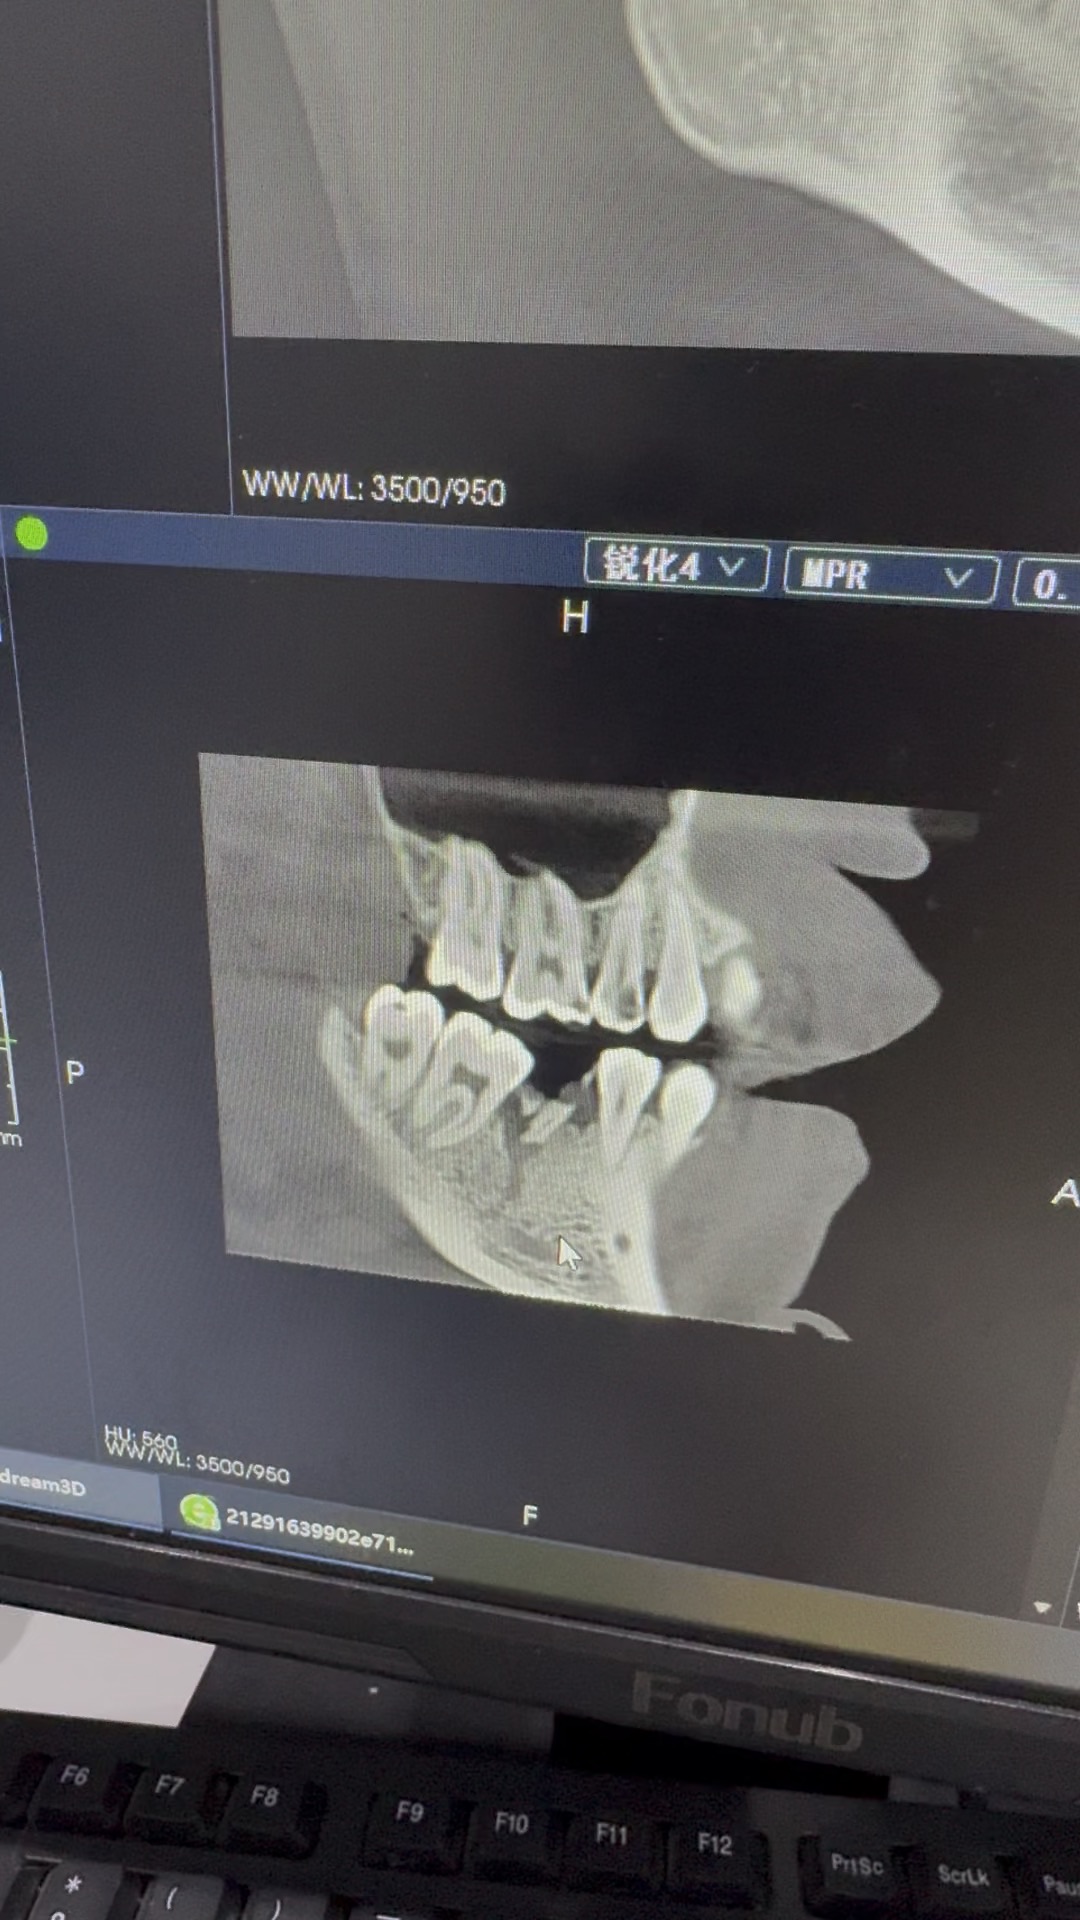

口腔2 条热帖已更新